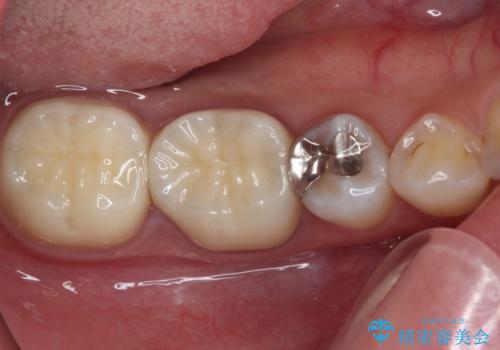

破折した歯を抜去し、インプラントによる補綴を行うこととしました。

銀歯の下のむし歯については、優先度の高い方からセラミッククラウンなどで治療していくこととしました。